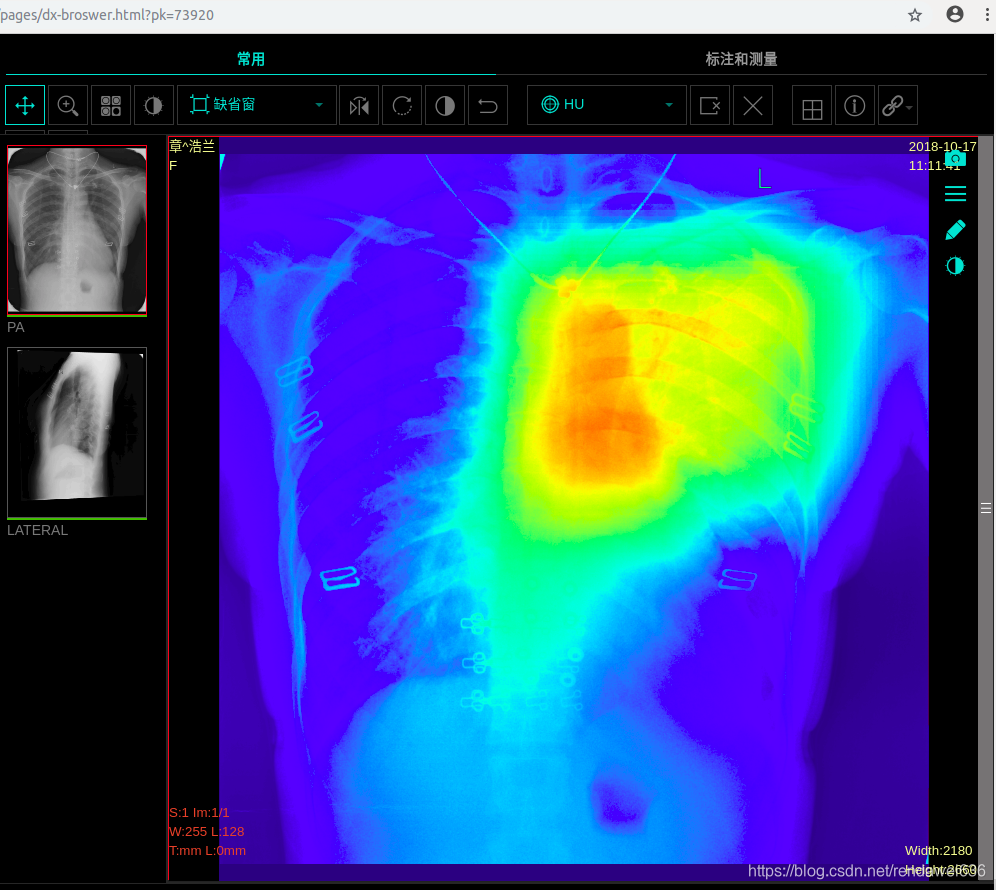

选取threshold为0.42,再将定位的图发送到前端H5,利用js将热力图和dicom灰度图进行合并后,显示如下

对应的老师报告如下

{"finding":"双侧胸廓大致对称。右上肺可见斑点及索条状密度增高影,边界清晰。余肺内未见其它异常阴影。肺门形态、大小及位置未见异常。纵隔无增宽表现,位置居中无移位,心影不大,形态未见异常。双侧膈肌光整,肋膈角锐利。片内所示胸廓骨骼及胸壁软组织无异常表现。","result":"右上肺结核,病灶基本纤维化、钙化。"}